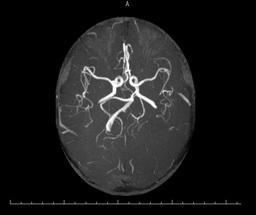

之后,医生为殷阿姨完善了其他检查,颅脑海马+MRA显示:1.双侧基底节区多发腔梗灶;2.脑白质变性;3.幕上(包括双侧海马)弥漫性脑萎缩,以左侧颞叶为著; 4.脑MRA检查提示脑动脉粥样硬化(图一)。颅脑ASL提示:全脑3D-ASL序列检查提示左侧额颞顶枕叶及右侧颞顶枕叶多发稍低灌注区,以左侧大脑半球为主(图二)。

头颅MRA图一